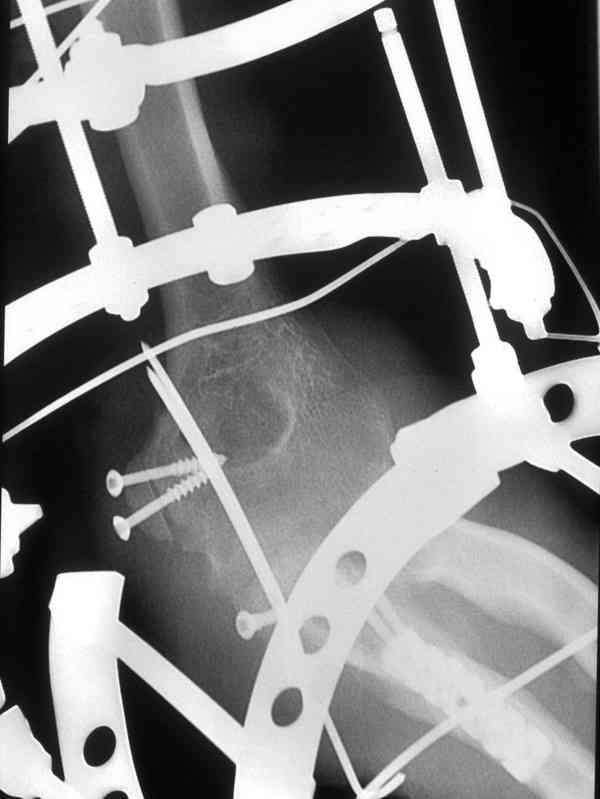

Со слов больного, травму получил при падении в подъзде на ступеньках.

Больной был прооперирован.Протеза головки лучевой у нас нет. Решили с локтевой костью пока ничего не делать. Выполнили операцию по востановлению связочного аппарата локтевого сустава(см.схему)- модфикация метода W.E.Spring,сухожилие мы фикстровали к винту на локтевой.

Естественно ревизия сустава и удаление рубцово-хрящевидных тканей.Затем наложили аппарат Илизарова с шарнирами. Первые 2 дня сустав был фиксирован трансартикулярно 2-мя спицами, затем спицы удалили. И больной начинает движения в аппарате.

Прилагаюся послеоперационные рентгенограммы.

Планиуем аппарат на 3-4 нед.